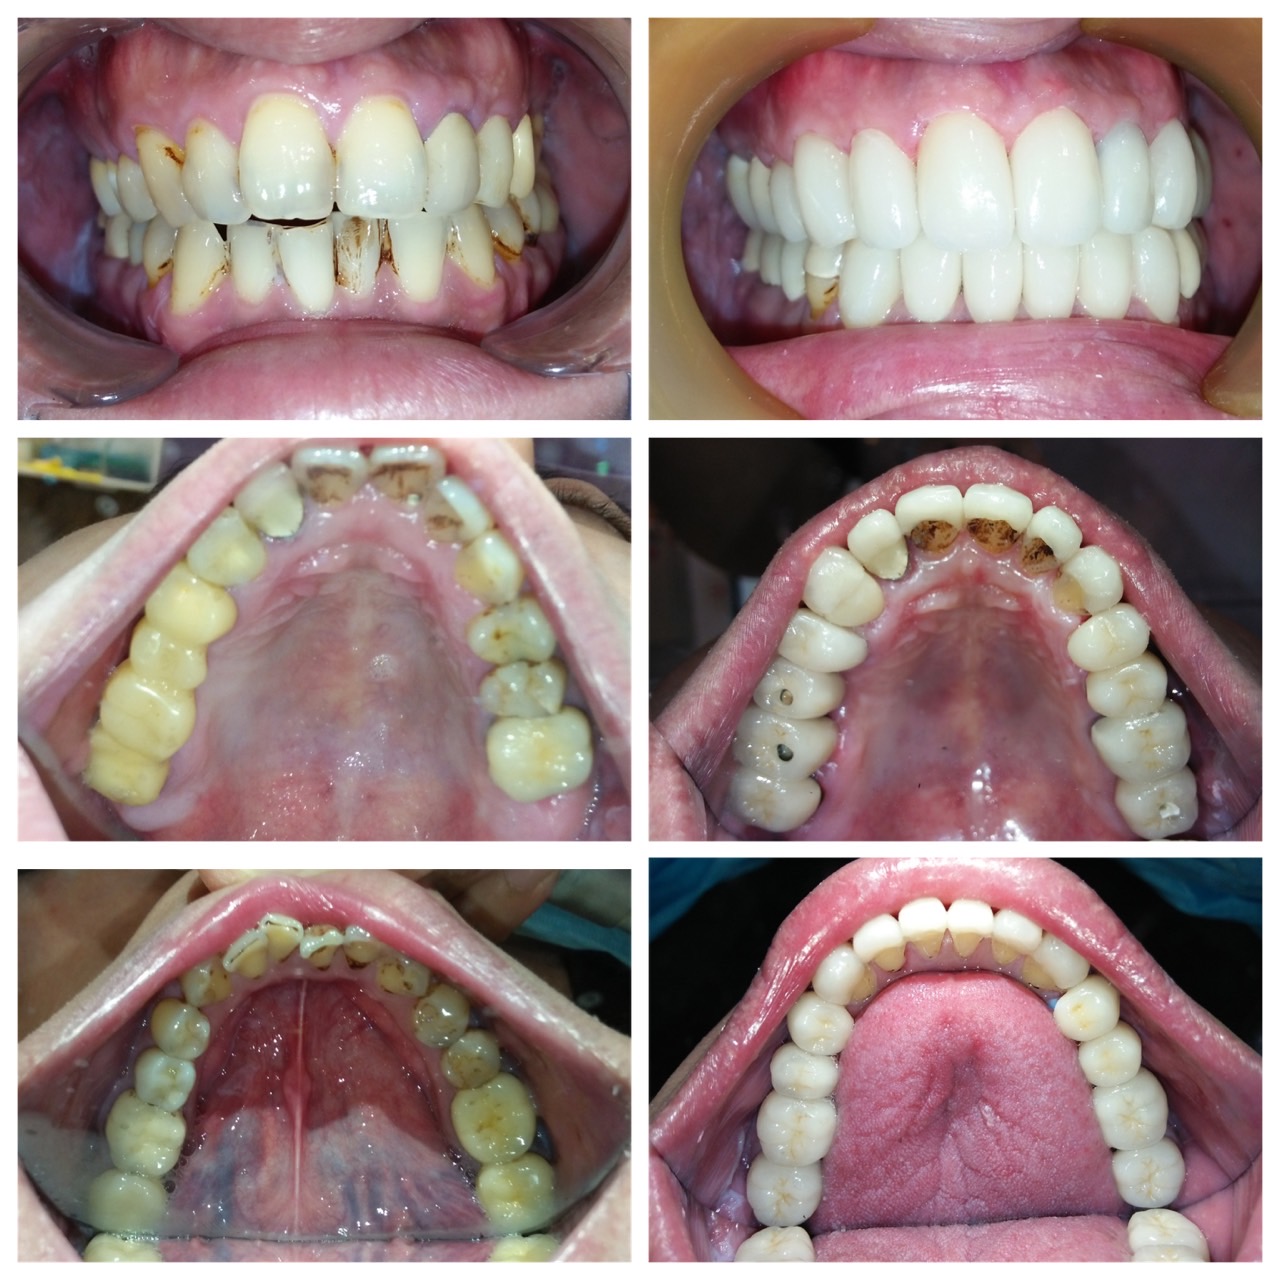

患者於原診所處理牙齒,僅是補牙、抽神經、做假牙的無限輪迴,牙齒壞了做牙橋,牙橋壞了補骨準備植牙,但因患者有疑慮,牙齒始終做不好,上顎假牙總是脫落、總是在看牙醫;決心換家評估。在聽過醫師仔細的分析後,決心要改變自己之前的觀念,接受醫師全口重建的治療方式。

這才發現原來補骨醫師技術有別,不是有補就好,蛀牙也不是一再重複處理讓牙齒神經反覆受刺激;需要先處理咬合、排列的問題,再將缺牙、蛀牙和前牙美觀合併處理,不但解決了牙縫塞東西造成蛀牙不斷,也讓牙齒排列改變改變外觀。

改變排列及牙齒上下相對位置,才能讓咬合和受力分配較佳並穩定,不會產生牙縫遭受直接衝擊的問題。

臨時的咀嚼一陣子並將咬合調順後,換成固定牙,更容易適應。

補骨後再植牙,讓牙齒地基有足夠的骨本,也讓自己擺脫總是在做假牙或做假牙的路上的命運。

改變觀念,跟上世界潮流的治療腳步,您可以擁有與展現與眾不同的笑容,讓人生更加精采!